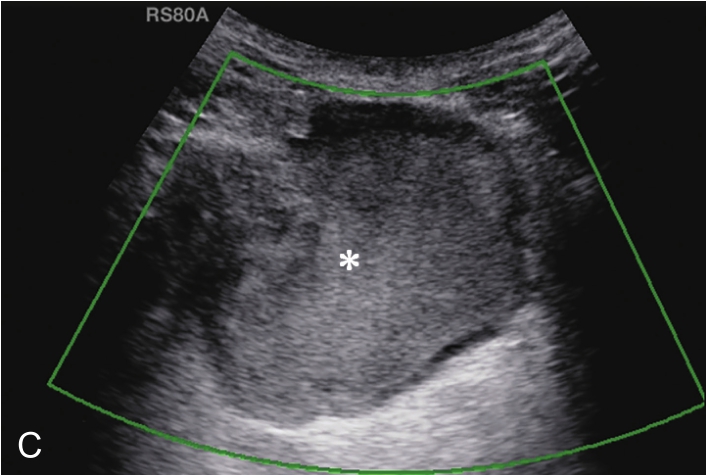

横放在肩关节前方,选择肩峰滑囊较厚或囊液较多处为靶目标(图2-1-2)。

▲ 图2-1-2 肩峰下-三角肌下滑囊炎超声图

星号:肩峰下滑囊增厚伴滑膜增生